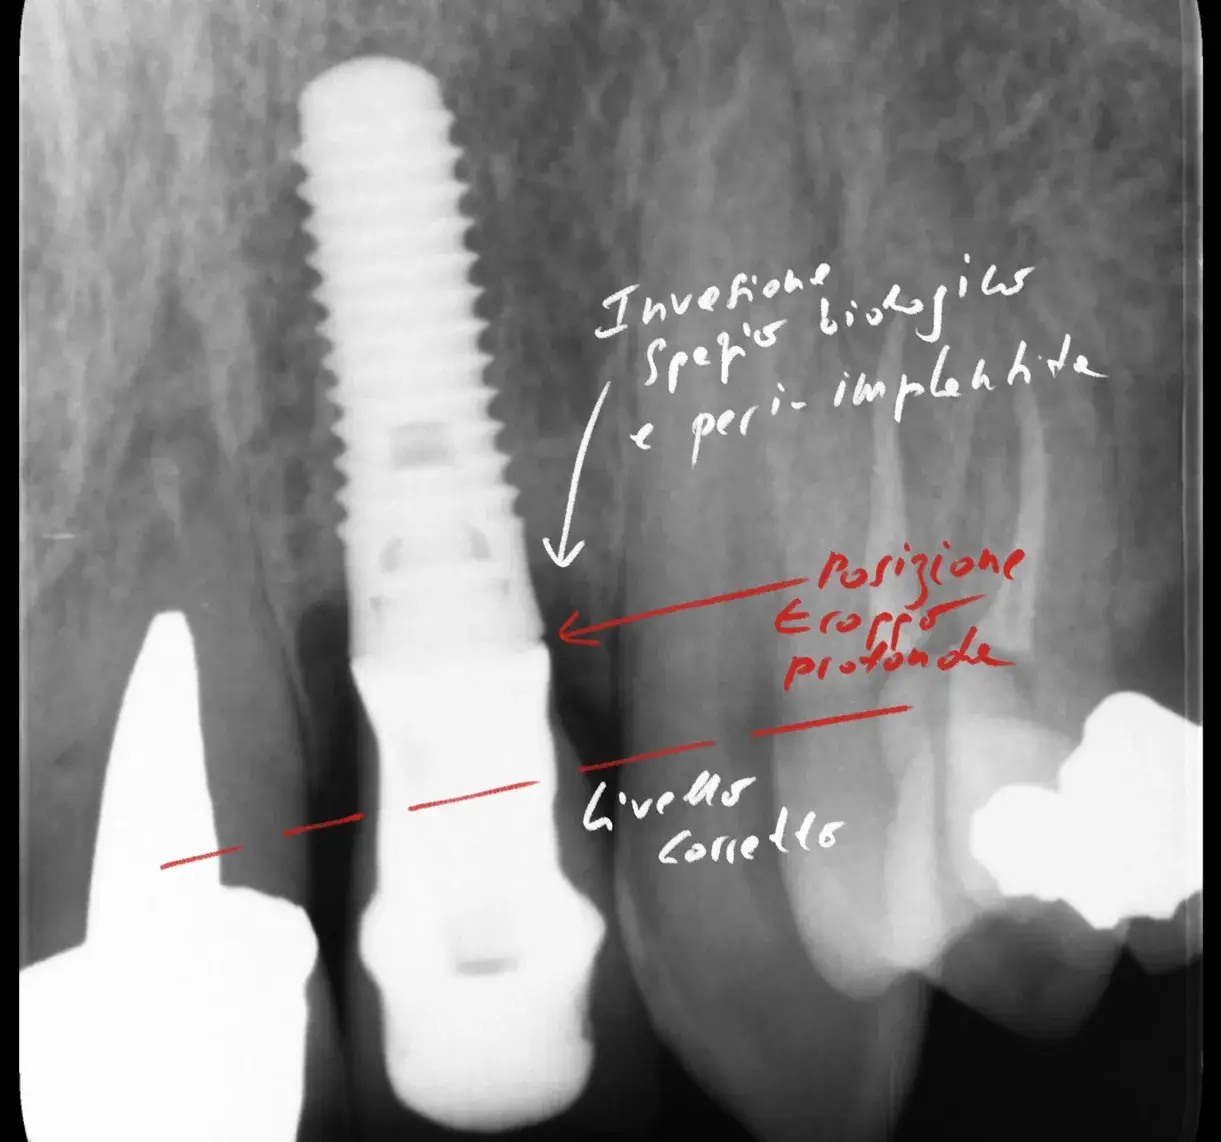

In breve — Nel 2024 Fernandes e colleghi hanno pubblicato su Microorganisms una revisione che aspirerebbe ad aggiornare i classici complessi di Socransky (E Haffajee) del 1998. Hanno nominato i nuovi cluster GF-MoR complexes. Sono sei, organizzati per condizione clinica invece che per patogenicità. Includono più di 250 specie batteriche, e evidenziano similitudini microbiologiche tra parodontite e peri-implantite.

Ma il punto più interessante è un altro. I sette batteri più rilevanti nella parodontite sono gli stessi nella peri-implantite. Stessi nomi, percentuali simili, stessa gerarchia. Sono tutti Gram-negativi.

Questo fatto, da solo, spiega molte cose. Spiega perché i pazienti con storia di parodontite hanno un rischio più alto di peri-implantite. Spiega perché le strategie terapeutiche per le due condizioni tendono a convergere. Spiega perché il mantenimento igienico funziona in entrambi i casi.